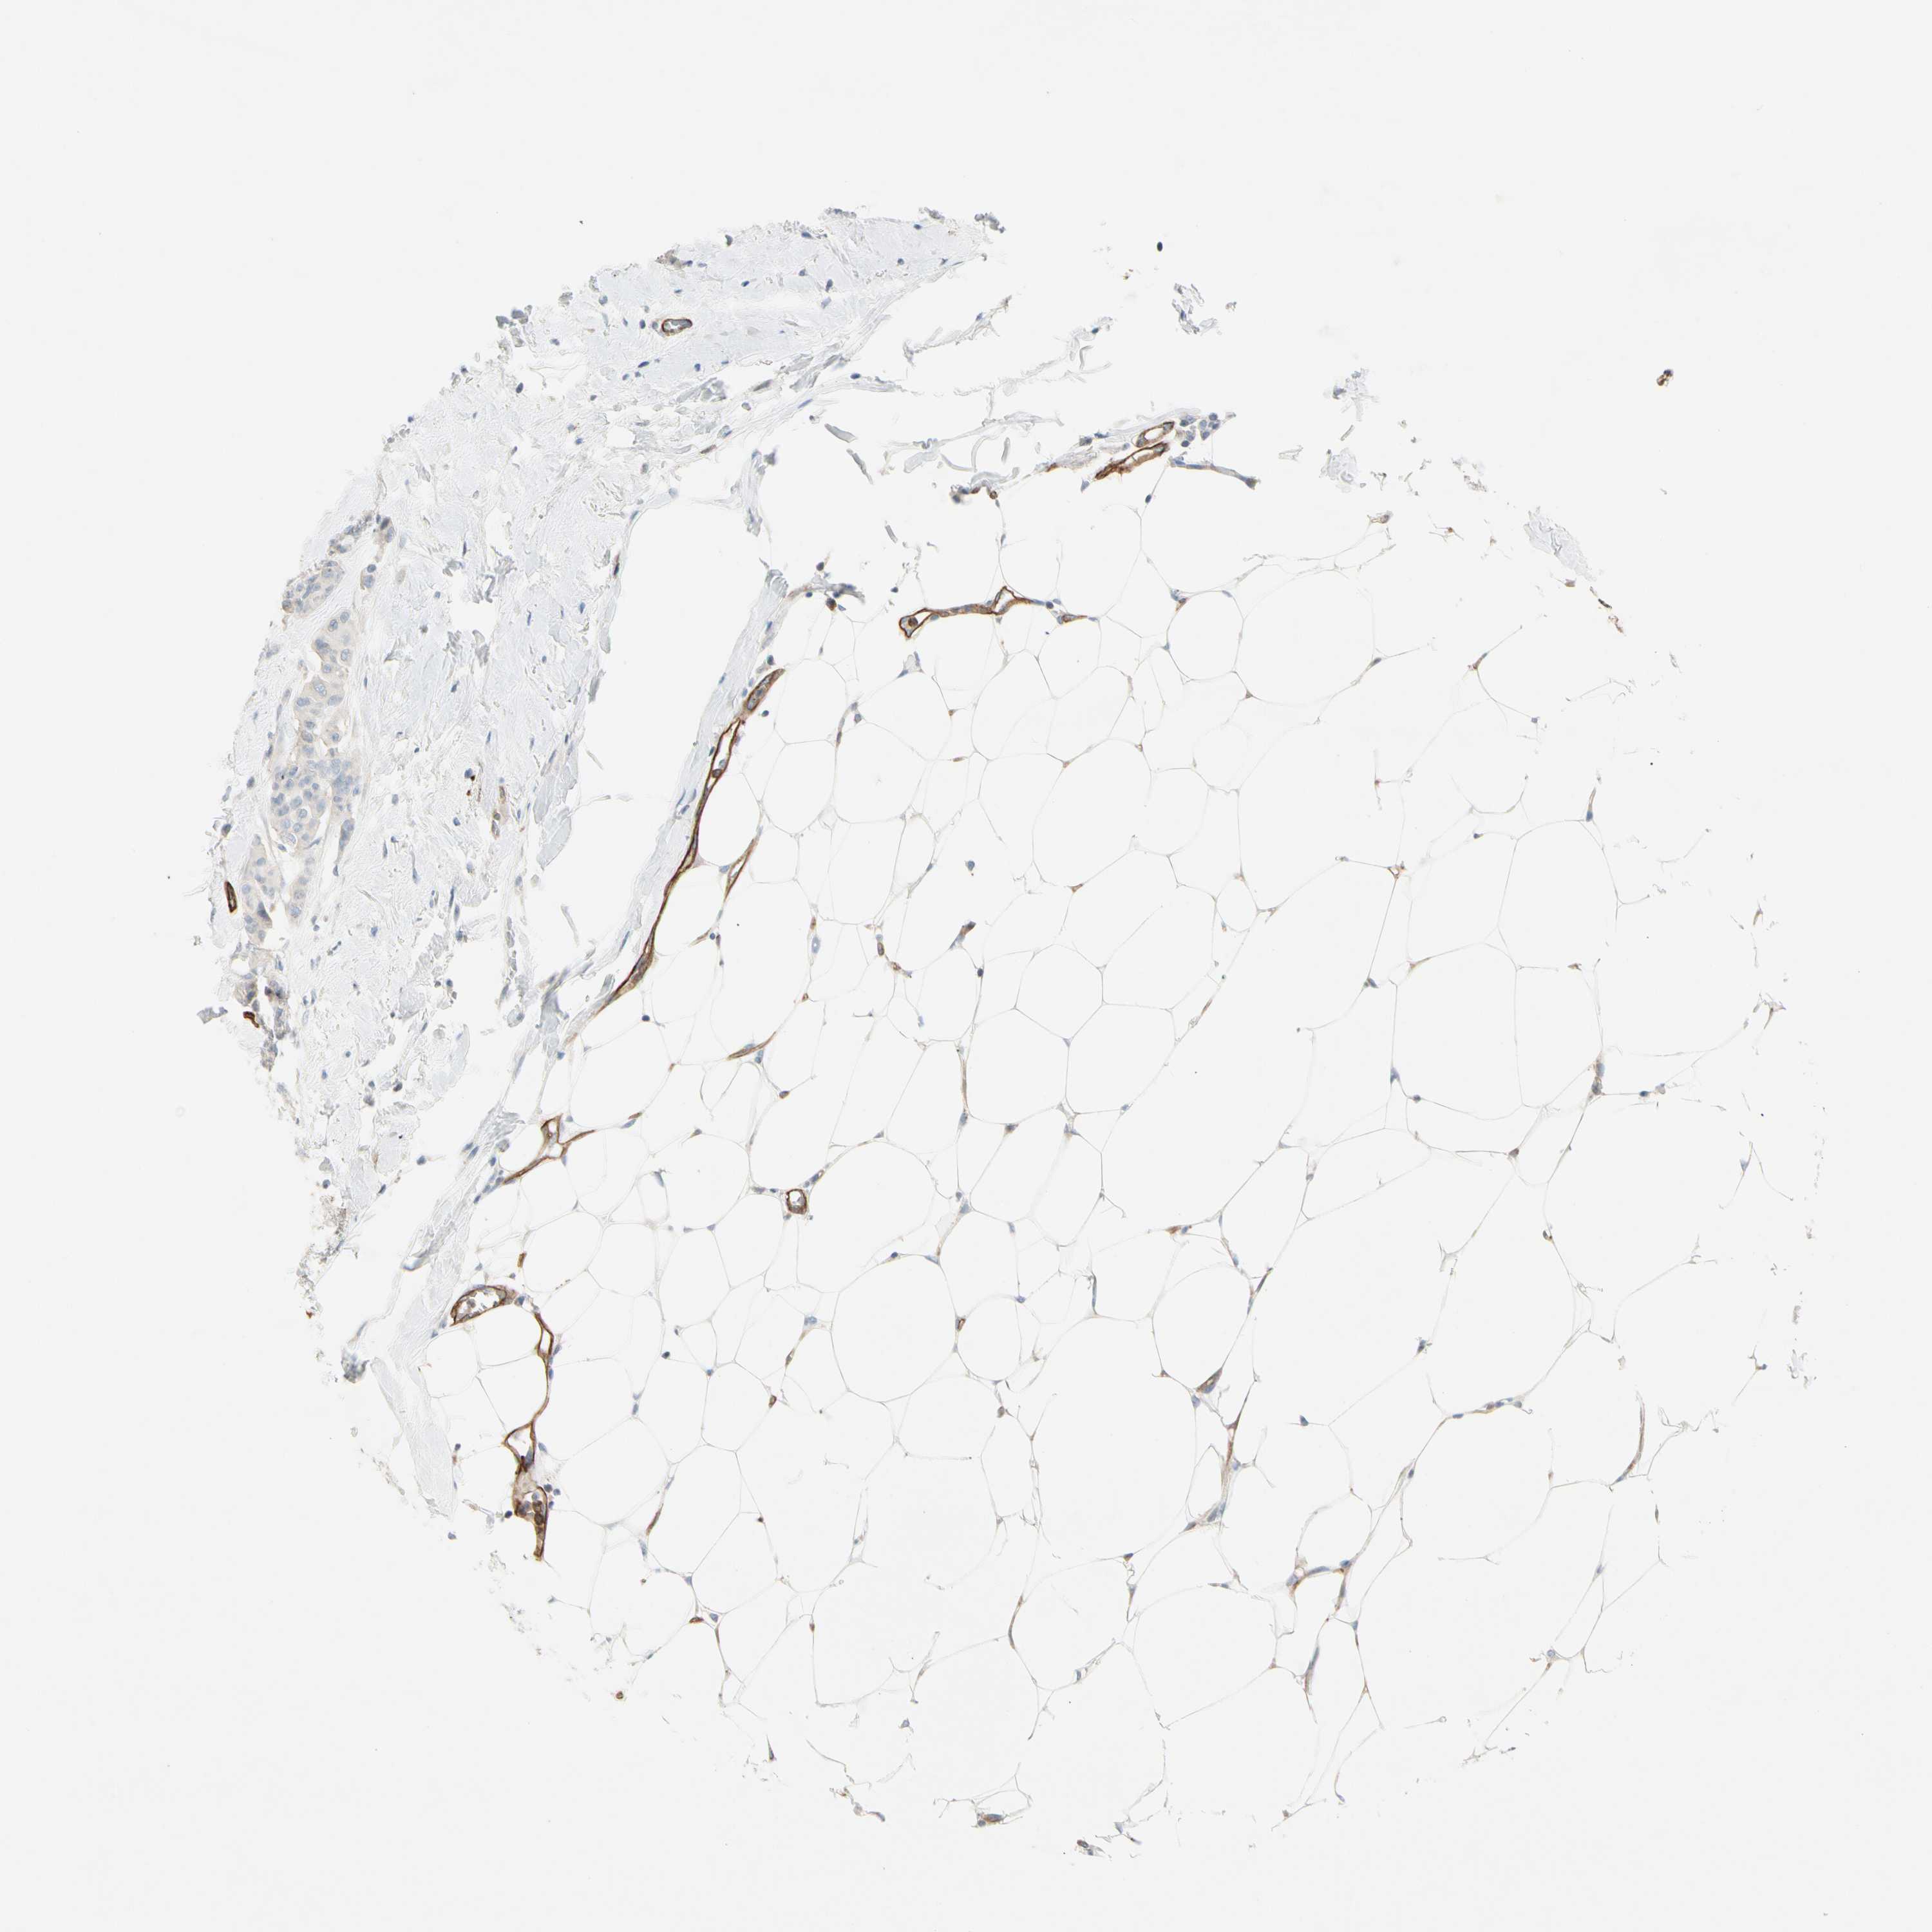

CANCER BREAST CANCER Show tissue menu

BRCA TCGA BRCA VALIDATION PROTEIN EXPRESSION

ANTIBODIES

AND

VALIDATION